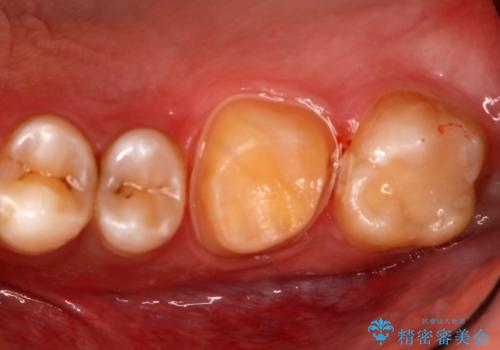

- 右上下6番の銀歯のやり変えを希望された患者様です。

切削量・形態を考慮し、上はセラミッククラウン、下はセラミックインレーでの治療を選択しました。

上はう蝕が歯頚部まで達していたのでクラウンでの治療を選択しました。

銀歯直下もう蝕が進行していたので全て除去した上でCRにて裏層しています。

下はクラウンほど切削量が多くないと判断し、インレーでの治療を選択しました。